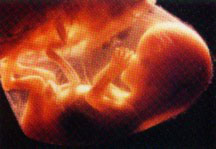

А ось і обіцяне зображення: малюк смокче свій великий палець. Втім, це не остання фотографія такого роду. (оскільки дана звичка зберігається аж до пологів)

Фотографія: Ленарт Нілсон